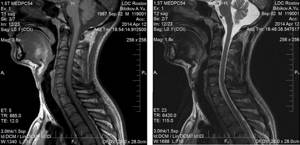

- КТ позвоночника, чтобы найти причину развития болезни с учетом мельчайших изменений;

- МРТ (при отсутствии противопоказаний), чтобы обнаружить изменения хрящей, нервов и сосудов;

- магнитно-резонансную томографию (МРТ) головы и шеи для оценки клеточной структуры мозга;

- МРТ шейного отдела позвоночника;

- компьютерная томография.